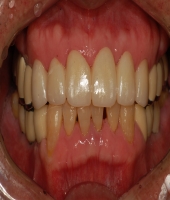

| ● 진료과목 : [심미보철] 돌출치아의 치료

| ● 내용 : 사고로 인한 돌출치아의 치료 |